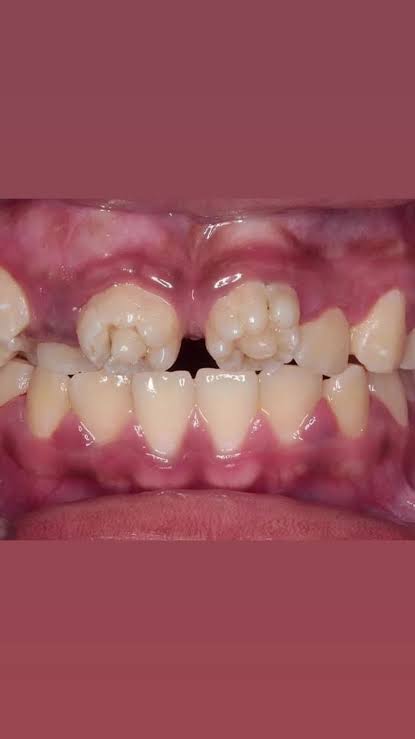

梅毒なんてまだあるのか…

ギザ歯の子って梅毒なんだ…

まず先天的にこの形になる事があるのを今知った

ちょっとヘラった人がやる人体改造の一種とばかり

ハッチンソン歯でググったけどこんな綺麗に全部ギザ歯になる?ってなった

>ちょっとヘラった人がやる人体改造の一種とばかり

先天性梅毒なせいでヘラったと考えられる

>母体から感染するって事…?

もちろんそうだ

妊娠中に梅毒に感染して子供に伝染るのが先天梅毒

基本的に抗生剤で治せる大人の梅毒とは話が違う

>ギザ歯の子って梅毒なんだ…

先天梅毒だとギザ歯になるが

ギザ歯だからと言って先天梅毒とは限らない

円錐歯は外胚葉性異形成症にも見られるからはっきりとしない

こういう歯の形態異常に関する問題は国試終わったばっかの歯学部生が一番知ってると思う